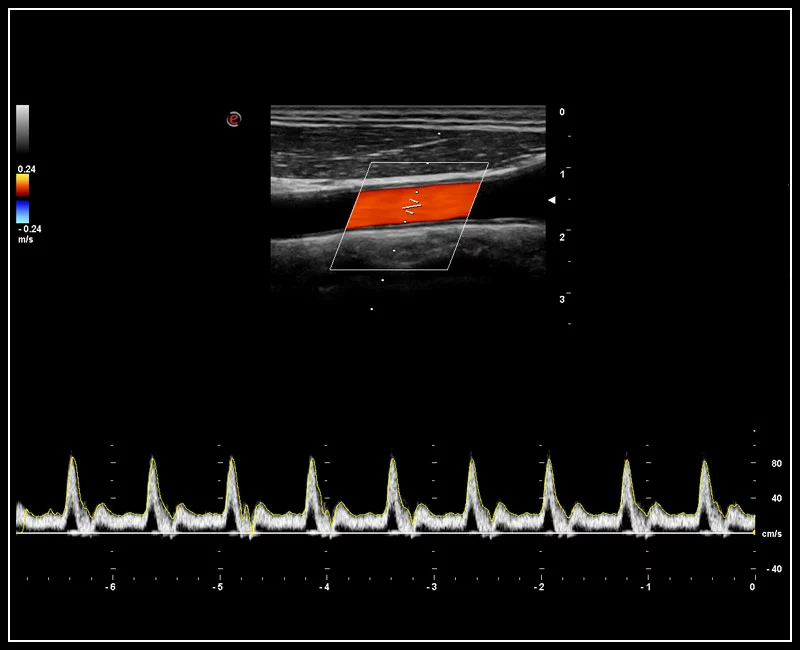

Q7 - CV Vascular

Q7 - CV Vascular